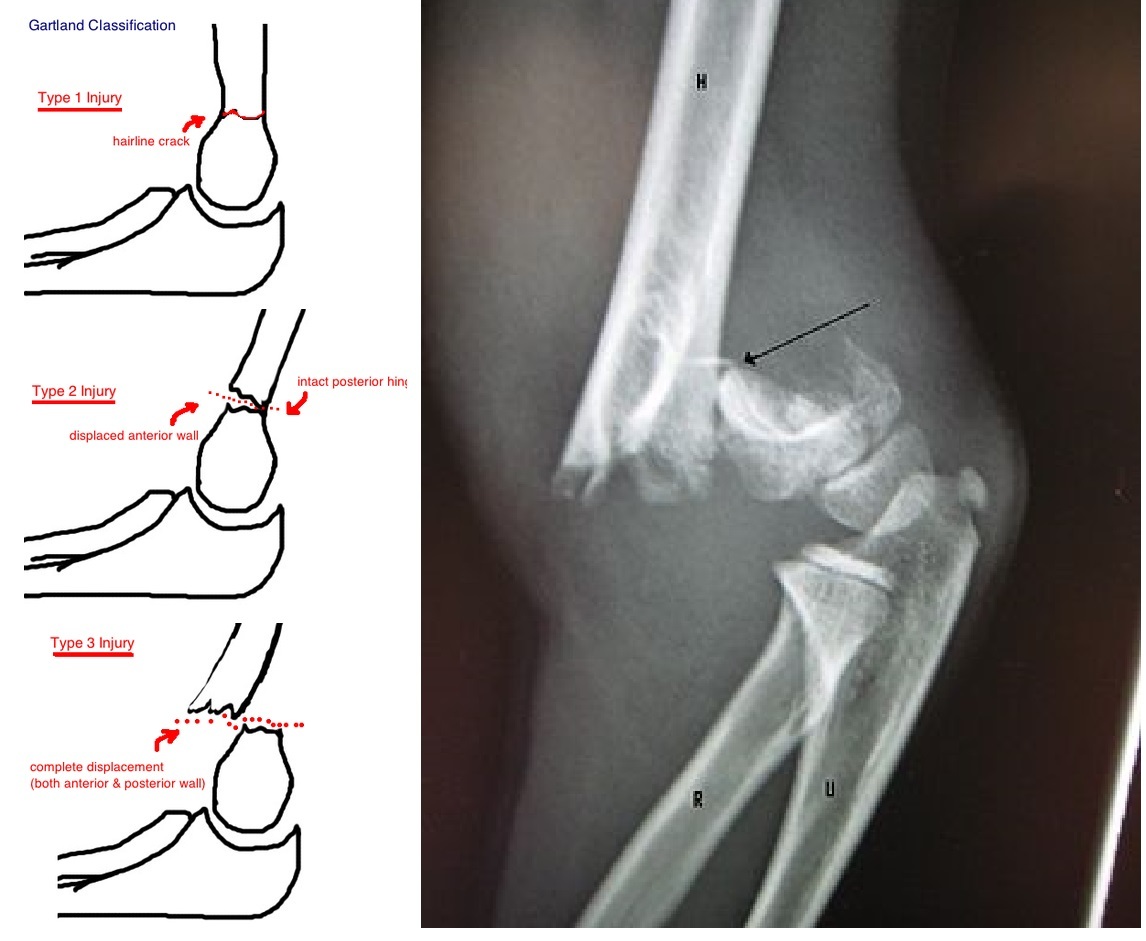

Supracondylar fractures usually occur in which age group?

Children